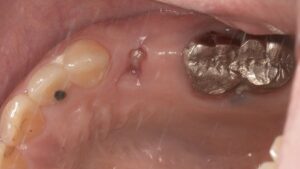

術前です。

埋入は骨のある部分に行いましたので 、安全に行えます。抜歯窩は少し削って親知らずが埋まるような穴をあけます。